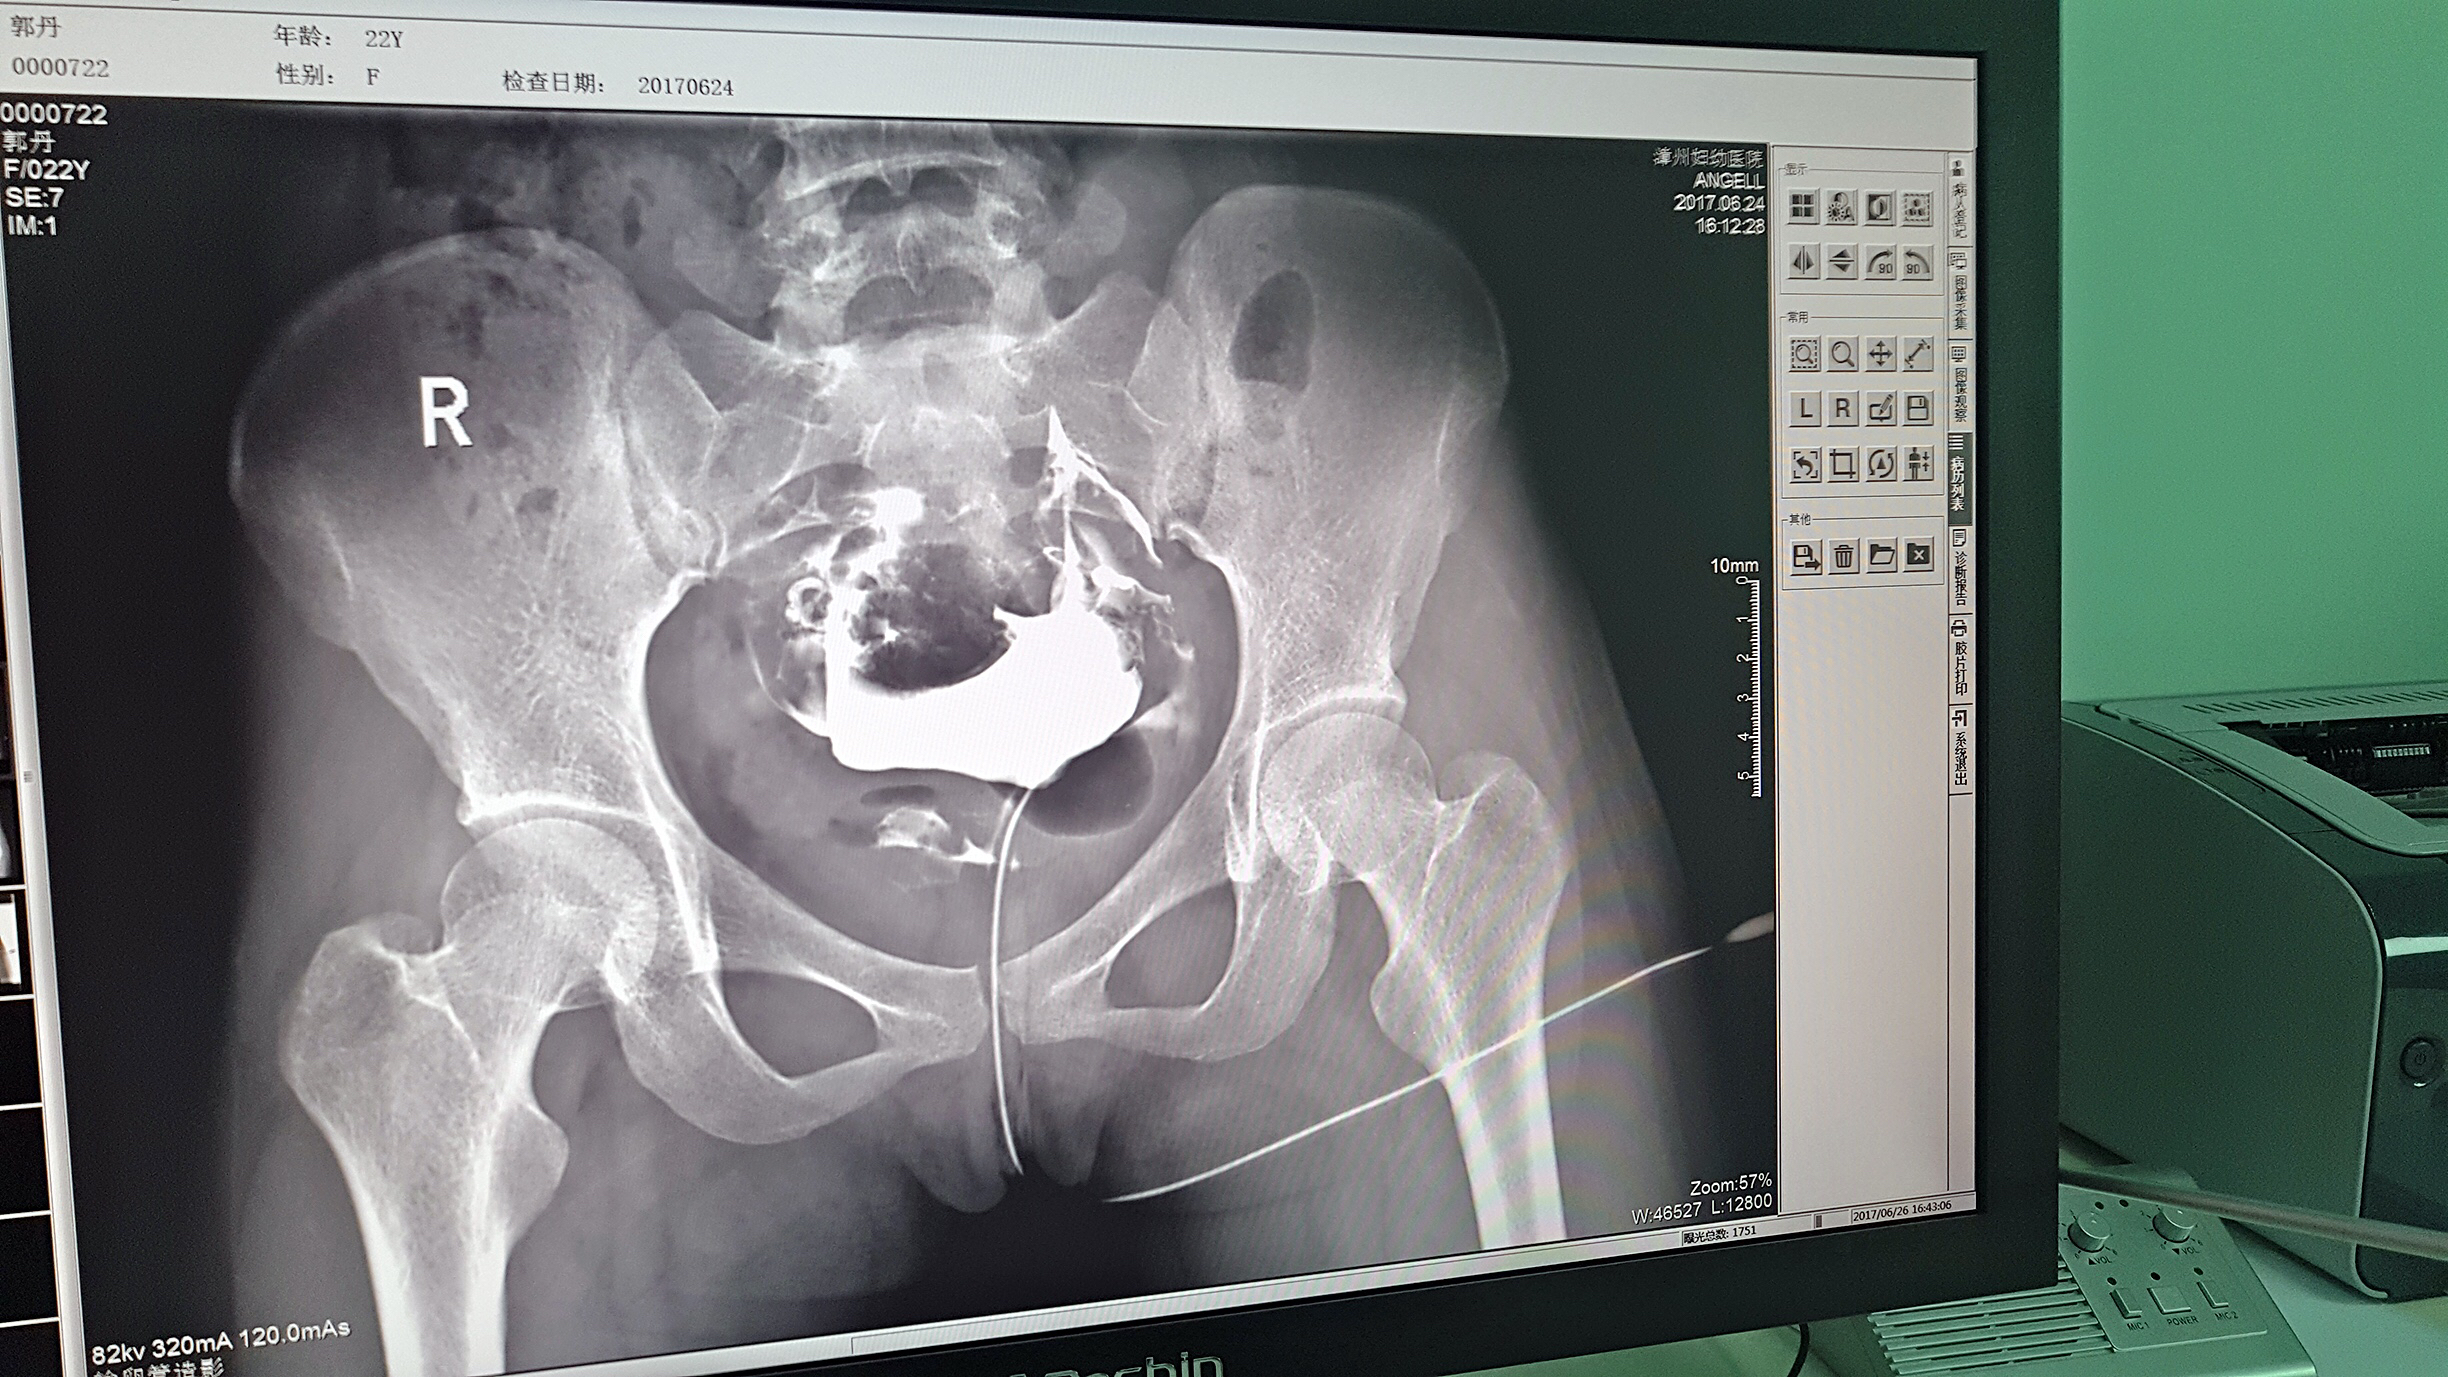

但是这家医院一直面临一个问题,妇科中输卵管检查无法完成。因为其使用的是静态DR,无法做输卵管造影检查,患者不得不前往其他医院继续检查,使得医院留不住患者,造成一笔损失。久而久之,患者可能为了图方便,直接去了其他医院治疗,这对医院经营的影响是巨大的。

目前设备除了用于常规拍片之外,主要用于输卵管造影检查,平均每个月有超过20个患者在漳州妇幼医院做输卵管造影检查。在此之前,漳州市只有市医院、175解放军区医院等大三甲医院才能做输卵管造影检查,这不仅让三甲医院人满为患,而且下级医院却因为不能做某项检查而造成资源浪费。因为有了设备,漳州妇幼医院可以满足患者的一些特殊检查需求,已经有很多患者慕名而来。

漳州妇幼医院放射科的陈主任日常跟这台设备打交道是最多的,他最有发言权。在388vip太阳集团科技的回访中,陈主任说:这台设备具备先进的诊断功能,操作方便,能够拍摄出清晰的影片,进而对患者病情能够实现精准诊断。同时在医院对患者诊断能力方面有较大提升,留住了大量患者,为患者提供了更好的医疗服务。